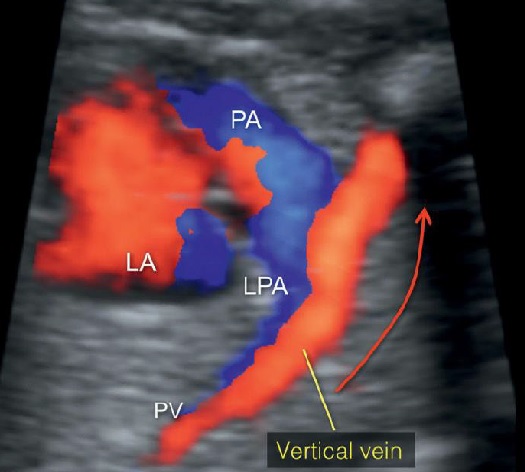

Thể trên tim (type I: supracardiac)Là bất thường phổ biến nhất của bất thường kết nối tĩnh mạch phổi toàn phần. Cả 4 tĩnh mạch phổi kết nối với nhau tạo nên tĩnh mạch thu thập (confluent vein) phía sau tâm nhĩ trái sau đó kết nối qua tĩnh mạch dọc trên (vertical vein) rồi đổ vào tĩnh mạch cánh tay đầu hoặc tĩnh mạch vô danh rồi cuối cùng đổ về tĩnh mạch chủ trên để về nhĩ phải (Hình1B).

Tình trạng này có thể quan sát thấy bằng cách phát hiện thấy tĩnh mạch hợp lưu phía sau nhĩ trái (Hình 1B). Tại mặt cắt 3 mạch máu - khí quản, ta có thể thấy một mạch máu thứ tư đó là tĩnh mạch dọc, nó được nhìn thấy ở vị trí giải phẫu giống như một tĩnh mạch chủ trên bên trái (LSVC) (Hình 1B). Nhưng trong tồn tại tĩnh mạch chủ trên trái (PLSVC), máu từ tĩnh mạch cổ trong trái (left internal jugular vein) chảy theo chiều từ trên xuống thông qua LSVC về tim, còn dòng máu trong tĩnh mạch dọc trên trong thể trên tim của TAPVR lại chảy theo chiều ngược lại từ tim lên phía đầu. Doppler màu trên mặt cắt 3 mạch máu khí quản cho phép ta đánh giá chiều dòng chảy của các cấu trúc giải phẫu này.

HÌnh 9: (A) Sơ đồ bất thường hệ thống hồi lưu tĩnh mạch phổi hoàn toàn. (B) mặt cắt ngang ngực của thể trên tim (type I: supracardiac – TAPVR). Hình ảnh B tương ứng với mặt cắt theo đường màu xanh ở hình A. Mũi tên xanh chỉ hướng dòng máu ở tĩnh mạch dọc (vertical vein) chảy vào tĩnh mạch chủ trên (SVC). Hình B cho thấy hình ảnh tĩnh mạnh dọc (vertical vein) nằm ở bên trái động mạch phổi (PA) và tĩnh mạch chủ trên (SVC) nằm ở bên phải động mạch chủ (AO). Doppler màu cho thấy chiều cùa dòng máu trong tĩnh mạch chủ trên (SVC) và tĩnh mạch đứng dọc (vertical vein) là ngược nhau. Điều này trái ngược với dòng máu trong tồn tại tĩnh mạch chủ trên trái (Persistent left superior vena cava PLSVC: Dòng màu trong tĩnh mạch chủ trên trái cùng chiều với dòng máu tĩnh mạch chủ trên phải -RSVC, cùng hướng về tim). RA: tâm nhĩ phải; LA: tâm nhĩ trái; IVC: tĩnh mạch chủ dưới.

Hình 12: Hình ảnh thai nhi có bất thường hồi lưu tĩnh mạch phổi toàn phần thể trên tim (supracardiac) (A) Sơ đồ 4 tĩnh mạch phổi đổ vào tĩnh mạch hợp lưu (confluent vein); (B) hình ảnh mặt cắt tương ứng theo đường màu ở sơ đồ (A). Các mũi tên nhỏ ở A và B thể hiện tĩnh mạch phổi (PV) đổ vào tĩnh mạch hợp lưu (confluent vein - mũi tên lớn) sau đó đổ vào tĩnh mạch dọc (Vertical vein - vv - mũi tên rỗng) rồi đổ vào tĩnh mạch chủ trên (SVC) thay vì đổ vào nhĩ trái (LA). Hình ảnh 3D Doppler tương ứng (hình 13).

Hình 13: Siêu âm 3D Doppler màu của lồng ngực thai nhi có TAPVR – type I. Hình ảnh tĩnh mạch phổi hội lưu về tĩnh mạch dọc sau đó kết nối với tĩnh mạch cánh tay đầu (brachiocephalic vein) chứ không phải đổ vào tâm nhĩ trái (LA). PV: tĩnh mạch phổi; PA: động mạch phổi.